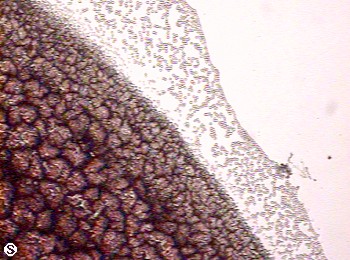

The fine lines in the foreground are a result of acute dic from oxidative stress.